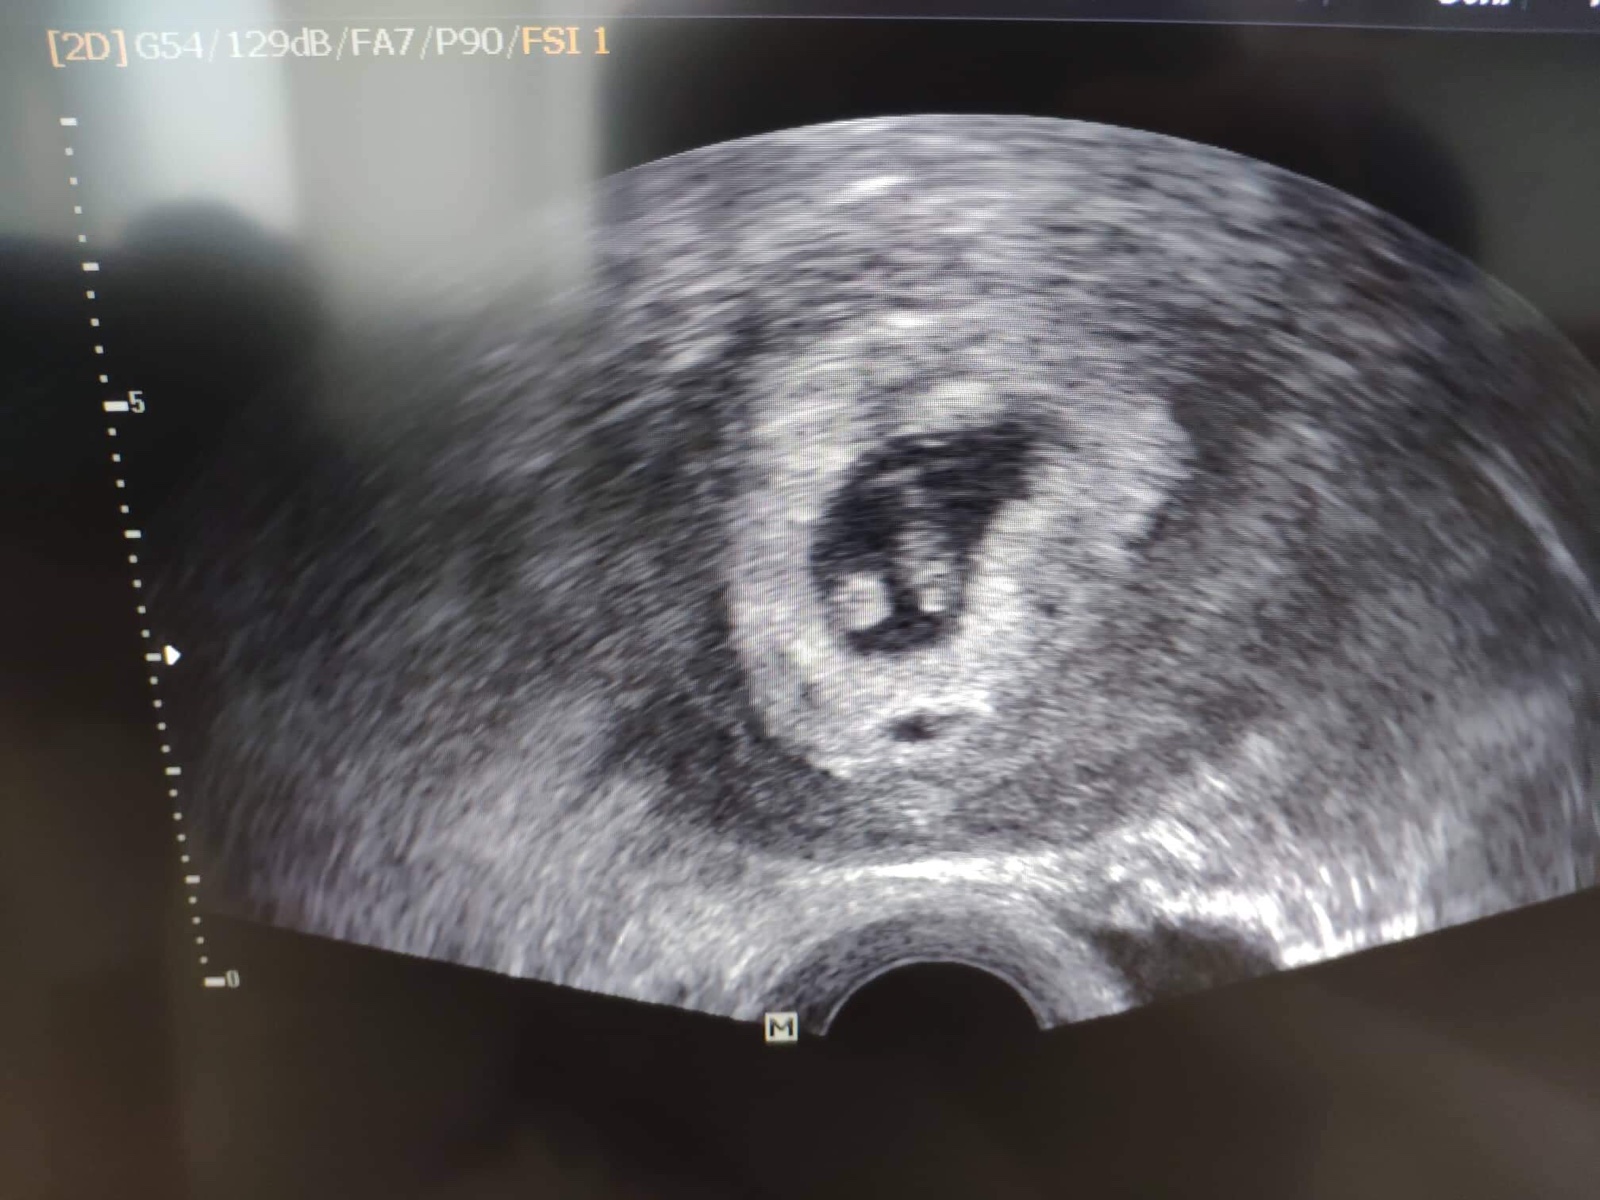

Ahoj holky, ja dnes ultrazvuk a bilo i srdicko ❤️

Za tyden jdu zas